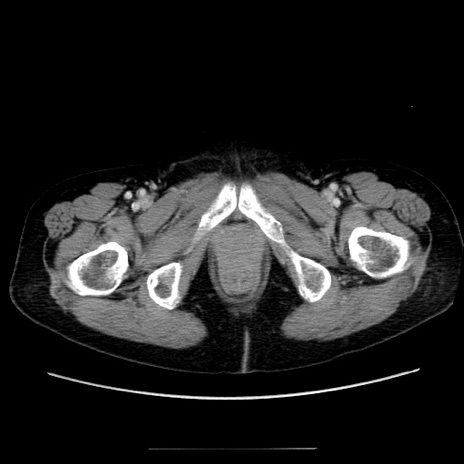

冠状断像

症例5(横断像)

【症例】70歳代女性

【主訴】お腹が張る

【現病歴】1週間くらい前から腹部膨満の自覚あり。昨日夜から増悪したため、本日救急外来受診。

【身体所見】意識清明、BT 36.5℃、BP 165/106mmHg、HR 80bpm、SpO2 98%、腹部:膨満、軟、自発痛・圧痛なし、触診にて不快感あり、腸蠕動音:減弱

【データ】WBC 12600、CRP 1.04